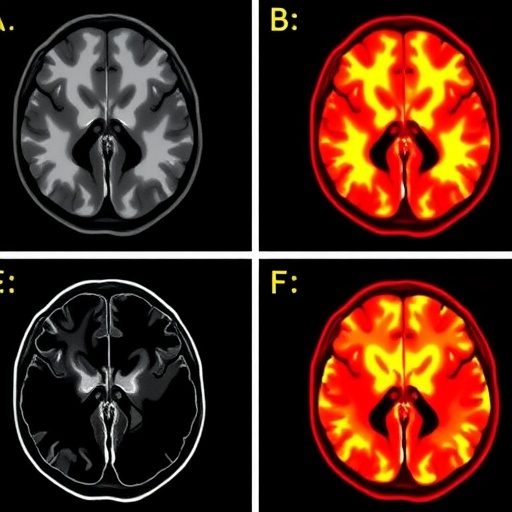

Pedunculopontine nucleus (PPN), situated in the brainstem, is a fundamental hub for cholinergic neurons known to regulate arousal, motor control, and REM sleep. The cholinergic projections emanating from this nucleus reach the thalamus, a central relay station in the brain that modulates cortical activity and sensory information processing. In this study, the authors employed advanced neuroimaging and electrophysiological techniques alongside post-mortem histological analysis to map and characterize the integrity of the pedunculopontine-thalamic cholinergic pathway in subjects diagnosed with RBD.

The methodology uncovered significant degeneration and altered connectivity in cholinergic projections implicating a breakdown in the neural circuits responsible for REM sleep muscle atonia. Using targeted tracers and immunohistochemical markers, the study detailed how cholinergic terminal loss correlated with the severity of REM sleep muscle tone abnormalities. Functional MRI scans of RBD patients revealed decreased connectivity between the PPN and thalamic nuclei, suggesting a functional impairment that mirrors the structural degeneration observed microscopically.

Additionally, the integration of multi-modal imaging and neuropathological data sets a new standard for investigating brainstem-cholinergic circuits in human disease. This comprehensive approach enables precise localization of affected pathways and correlates these findings with clinical symptomatology, supporting a biomarker-driven model for early diagnosis and individualized treatment strategies in RBD and Parkinson’s disease.